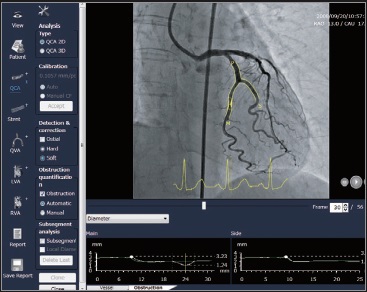

QCA* забезечує автоматичне виявлення контуру та аналіз області, що цікавить. Доступні різні методи калібрування, такі як по катетеру, по сфері та по відстані.

3D-QCA* виконує реконструкцію стенотично уражених коронарних артерій і дозволяє відображати кількісну інформацію поперечного перерізу. Можливий як, односегментний аналіз, так і аналіз біфуркації.

* опційно

CAAS vFFR (судинний фракційний резервний кровотік, так званий віртуальний) обчислює падіння тиску в коронарних судинах без необхідності використання провідника з датчиком тиску. Модуль vFFR будує 3D-реконструкцію на основі двох ангіографій і оцінює падіння тиску, в результаті чого отримує значення vFFR. Крім того, 3D-реконструкція дозволить оцінити ступінь тяжкості та відсоток стенозу.

Інформація про функціональне ураження:

Інформація про анатомічне ураження: